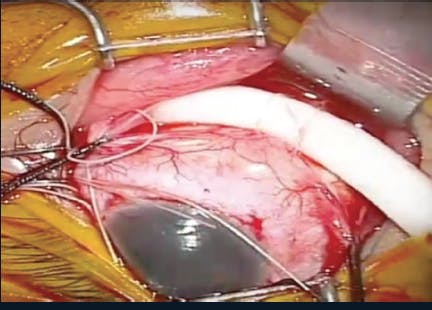

(http://bit.ly/0919MODScleralBuckle)) A silicone or plastic band is placed on the outside of the globe to indent the area of the eye with the detached retina. This alleviates pressure on the retinal break, allowing the tear to reattach to the wall of the eye.

(http://bit.ly/0919MOD) VitrectomyThe vitreous gel is removed and replaced with a bubble (eg, gas, silicone, air). Separating the posterior hyaloid from the retina relieves vitreoretinal tractional forces to facilitate RD repair.